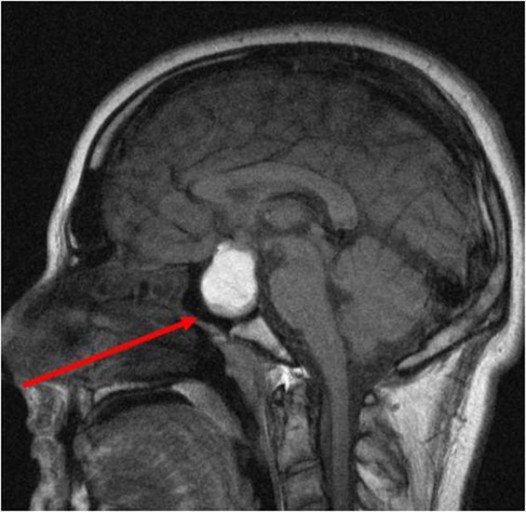

CT, MRI 검사를 통해 진단할 수 있고, 뇌하수체선종이 의심되는 경우, 뇌하수체에서 분비되는 호르몬의 양을 측정합니다.